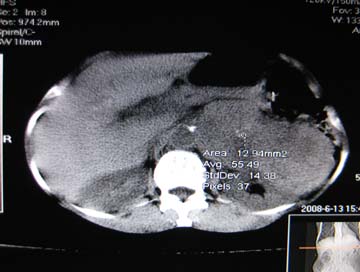

女,65岁,左上腹痛。

肝脏占位  脾脏及胰腺病变   请提供病史

肝脾胃左肾胰都显示不正常啊

病史不详,肝、脾、胰都有占位,谁是原发?

淋巴瘤及肝癌(转移瘤?)可不可以不用一元论解释呢。

肝脏 脾脏 胰腺都有病变.

胰腺癌伴脾脏侵犯并肝内转移可能性大  建议增强扫描  否则没有确凿的依据

考虑姨尾癌,腹膜后转移\\肝转移

没有病史,没有强化,那就只有猜了,我看病灶很像肝、脾及腹腔多发脓肿,这只是我的意见,

图像欠清,病灶与胃脾胰肾上腺关系显示欠清,建议增强,肝脏考虑转移瘤.

多脏器占位,腹膜后淋巴结增大,淋巴瘤?建议增强扫描